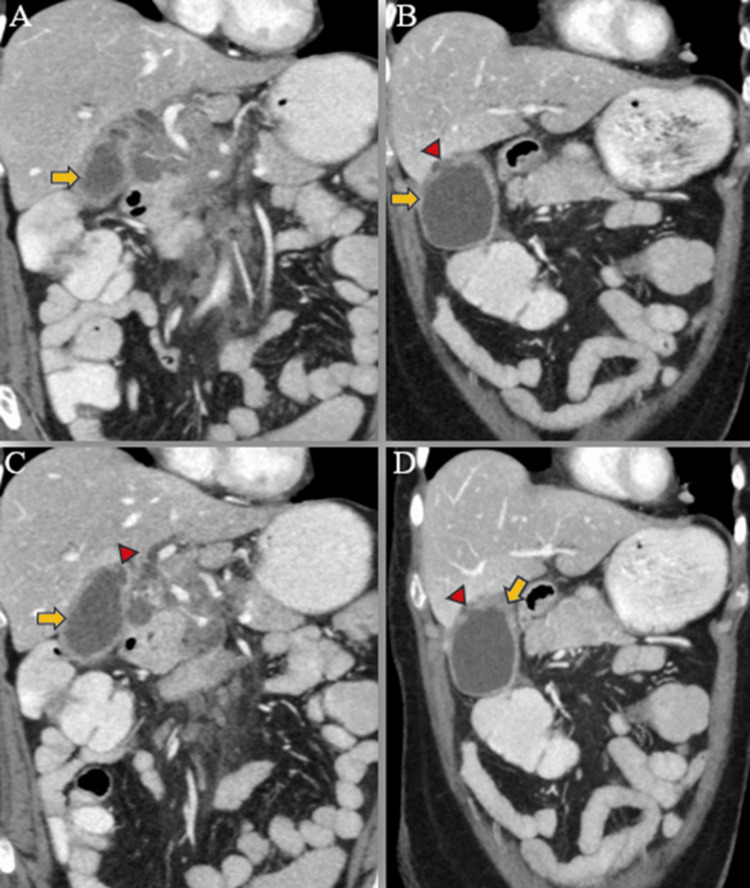

A triphasic computed tomography (CT) scan of the abdomen and pelvis revealed mild IHBR dilatation in both the right and left hepatic lobes. The gallbladder was overdistended, with mild wall thickening (4 mm), exhibiting post-contrast enhancement. Additionally, a small 5 mm defect was identified in the body region, accompanied by a well-defined hypodense fluid density lesion measuring approximately 13 x 6 mm adjacent to it. No radiodense calculus was detected. The proximal CBD showed dilation (8 mm) with mild eccentric wall thickening in the mid-CBD (maximum thickness 5 mm), showing post-contrast enhancement. The remainder of the CBD appeared normal in caliber and wall thickness (Figures 5–6).

Furthermore, multiple lymph nodes of variable sizes, demonstrating mild heterogeneous post-contrast enhancement, were noted at the porta hepatis, peripancreatic region adjacent to the pancreatic head, celiac region, aorto-caval region, pre-aortic, and left para-aortic region, with the largest measuring approximately 18 x 35 mm (anteroposterior x transverse) at the porta hepatis (Figure 7). Both adrenal glands appeared normal, and there was no evidence of ascites. The rest of the abdominal organs exhibited normal appearances.

Overall, these findings suggested a neoplastic mass originating from the mid-CBD, leading to an overdistended gallbladder, cholecystitis, and contained perforation in the body region, resulting in mild proximal obstructive biliary dilatation. Additionally, metastatic lymph nodes were identified at the porta hepatis and retroperitoneum, along with multiple lung metastases.